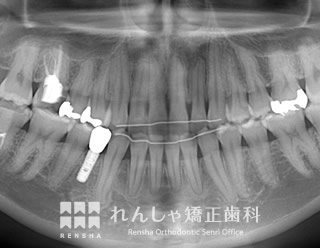

補綴前矯正(26歳 治療期間:2年2か月)

右下の永久歯が先天的に欠損していたため、下前歯は右側に偏っていました。

左側の噛み合わせに大きな問題はなかったことから、右上前歯のがたつきを改善し、右下には1歯分のスペースを確保してインプラント治療を受けていただきました。

| 主訴 | 上前歯のがたつきと右下の永久歯が1本足りない |

|---|---|

| 診断名 | Angle Class I 叢生 |

| 初診時年齢 | 26歳10か月 |

| 装置名 | マルチブラケット装置 |

| 抜歯非抜歯 | 非抜歯 |

| 治療期間 | 2年2か月 |

| 費用の目安 | 約90万円+消費税(検査料金、都度の処置費用等も合わせた総額) |

| リスク副作用 | 歯の移動に伴う軽微な歯根吸収、歯槽骨吸収、歯肉退縮(いずれも本症例ではほぼ無し)、矯正器具装着中のカリエスリスク増大(本症例では臼歯にカリエスが発生し、その後う蝕処置) |